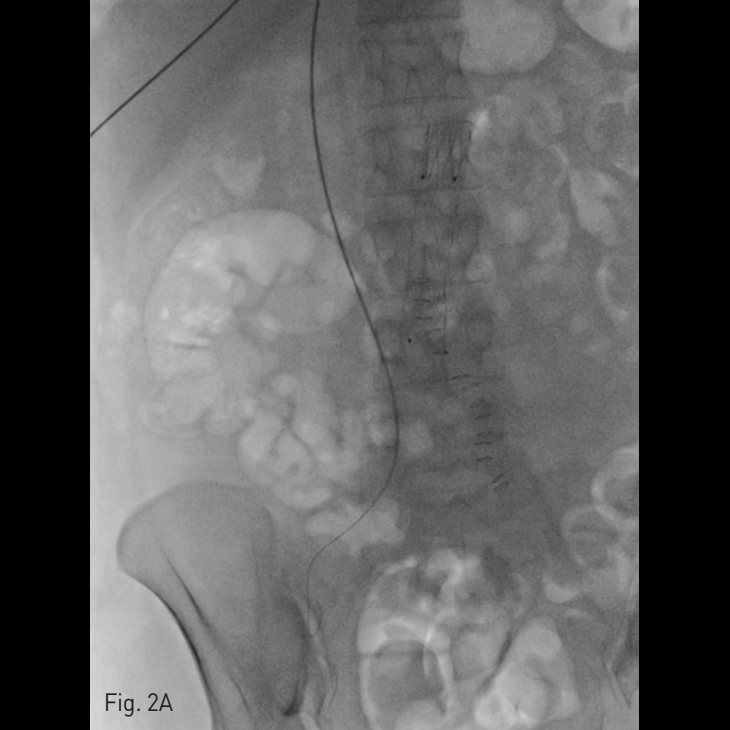

양측 내경정맥을 통한 정맥 조영술에서 상대정맥이 완전히 폐색되어 있으며 (Fig. 1A-B) 이를 대체하기 위해 우측 대퇴정맥에 투석용 카테터를 삽입하였지만 이 또한 10일 후 카테터 주변으로 혈전이 발생하였다(Fig 1C). 이어서 허리 경유 접근을 통해 투석용 카테터 삽입을 위해 하대정맥 천자를 시도하였으며 6 Fr sheath까지 들어간 후에 천자된 곳이 대동맥임을 알게 되어 대동맥에 stent-graft를 넣었다 (Fig. 2A). 투석이 급하여 일단 간정맥을 통하여 투석용 카테터를 삽입하였으나 (Fig. 1D) 이 역시 혈전으로 인한 기능 부전으로 수 차례 교환술을 시행하였다.

Fig. 2. Successful placement of translumbar tunneled dialysis catheter.

A. Through the transhepatic access, a 0.035-inch guide wire was advanced to the inferior vena cava. Note the previously inserted aortic stent graft (arrows).